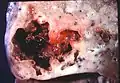

Pathology image of a lung abscess.